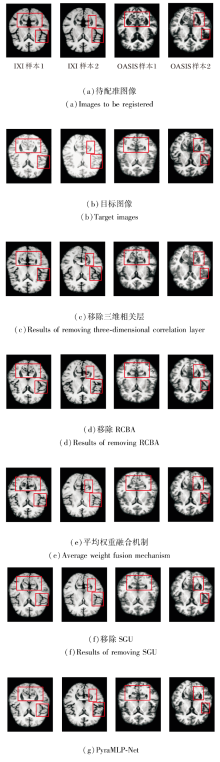

为了验证各子模块的必要性, 以完整模块为基准, 依次设置仅移除三维相关层、仅移除SGU、仅移除RCAB、将动态加权融合替换为平均权重融合机制这4个消融实验组.

在IXI、OASIS数据集上各自选取2个样本, 移除各子模块后图像配准结果如图17所示, 对PyraMLP-Net性能的影响如图18所示.由图可见, 移除三维相关层、SGU、RCBA及将动态权重融合机制替换为平均权重融合机制均会导致配准性能下降, 影响程度存在差异.

移除三维相关层的影响最显著, 原因在于三维相关层作为CMW-MLP的核心, 直接计算固定图像与移动图像特征的局部相关性并生成相关性特征图, 移除后PyraMLP-Net丧失对跨图像特征空间关联的有效感知能力, 仅能依赖特征的全局混合推理, 难以建立精准的像素级空间对应关系.

将动态权重融合机制替换为平均权重融合机制对网络配准性能的影响次之.动态权重融合机制可根据输入特征的形变尺度动态调整3× 3× 3、5× 5× 5、7× 7× 7多窗口分支的权重, 实现对不同尺度形变的自适应多范围依赖融合, 这对于准确捕捉脑部图像中混合存在的不同尺度形变至关重要.平均权重融合机制采用静态等权重分配, 完全稀释多窗口设计的核心适配优势, 导致PyraMLP-Net无法灵活应对不同尺度形变.

移除gMLP中的SGU对网络配准性能的影响处于中等程度.SGU作为gMLP的核心单元, 通过门控机制筛选关键空间特征, 强化窗口内像素的局部空间关联.移除后gMLP退化为普通MLP, 窗口内空间信息建模能力削弱, 但由于其作用仅局限于窗口内局部优化, 未触及配准核心逻辑, 故性能下降程度低于前两种操作.

移除RCBA对网络配准性能的影响最小, 该模块本质是通过通道注意力与残差连接筛选关键特征通道并优化影响特征表达鲁棒性的后处理环节, 缺失仅会导致特征表达精准度下降, 并未破坏配准的核心逻辑, 因此对整体性能的影响最轻微.